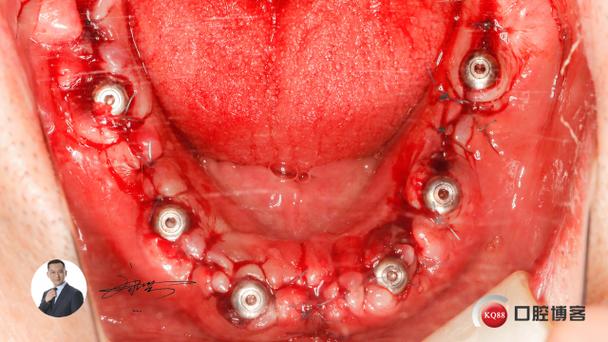

- 内提升术(冲顶术): 通过在缺牙区的牙槽嵴顶开一个小窗,用特制的器械(如骨凿、超声骨刀、液压器械等)小心地将上颌窦底骨壁和其上方的粘膜向上顶起,形成一个空间,然后植入骨粉,创伤相对较小,适用于骨高度缺损不是特别严重的情况。

- 外提升术(开窗术): 在上颌窦外侧壁开一个较大的窗口,像开“天窗”一样,将上颌窦粘膜完整剥离并向上推起,在下方植入较多的骨粉,适用于骨高度缺损严重的情况,但创伤和术后反应相对较大。